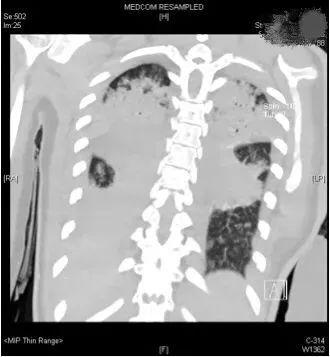

評估結果不容樂觀,呼吸機的支持水平要求很高,100%純氧條件下小文體內的氧分壓才勉強達標,持續高燒超過40攝氏度,CT復查提示兩肺幾乎全部實變,炎癥指標非常高。

(小文的影像檢查顯示,雙肺幾乎完全實變)